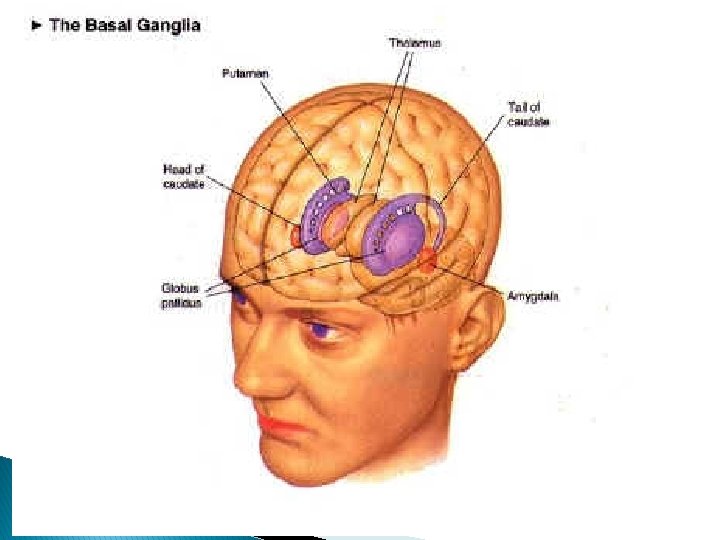

Helstu svæði heilans � Telencephalon ◦ Basal ganglia �Tekur til caudate nucleus, putamen og globus pallidus sem eru staðsettir undir heilaberkinum í hvelunum, og substantia nigra í miðheila �Kjarnarnir fjórir tengjast og eru mikilvægir í stjórnun hreyfinga �Þetta er svæðið sem bilar í Parkinsons-sjúkdómi